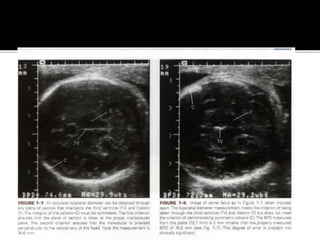

3.BIPARIETAL DIAMETER:

By the end of the first trimester, measurement

of the BPD becomes more accurate than the

CRL, which by that time reflects errors due to

biological variabilities.

In addition to BPD, corrected BPD, and HC are

the parameters which involve the fetal head.

Rules for measurement of the BPD:

 1. Correct plane of section is taken through

the third ventricle and paired thalami.

 2. the calvaria should be smooth and

symmetrical bilaterally.

 3.the cursors are positioned correctly.

 Measured from the outer edge of the cranium

nearest the transducer to the inner edge

farthest from the transducer.

 Corrected BPD =

square root of BPD X OFD/ 1.265

Significance: it represents the BPD of the

standard shaped head ( one with an OFD /

BPD ratio of 1.265) of the same cross

sectional area.